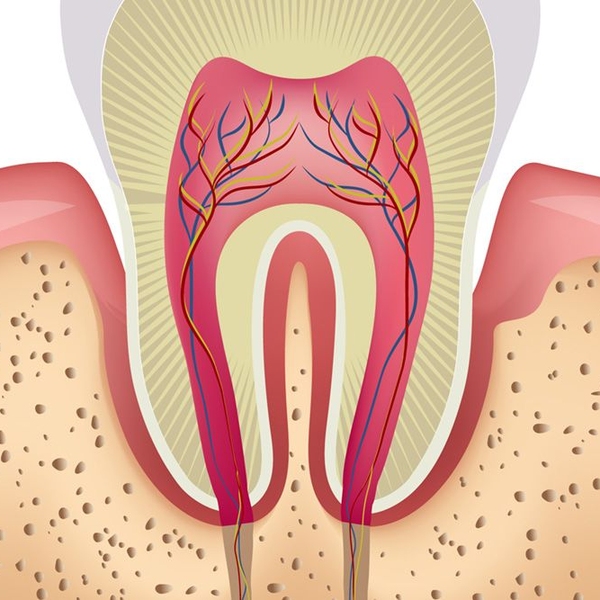

Root Canal Therapy

Root canal therapy is typically the most effective treatment for an infected tooth during which bacteria is removed and a crown is placed for protection. Thanks to modern techniques and effective local anesthesia, it involves little to no discomfort and ends the pain caused by dental infection.